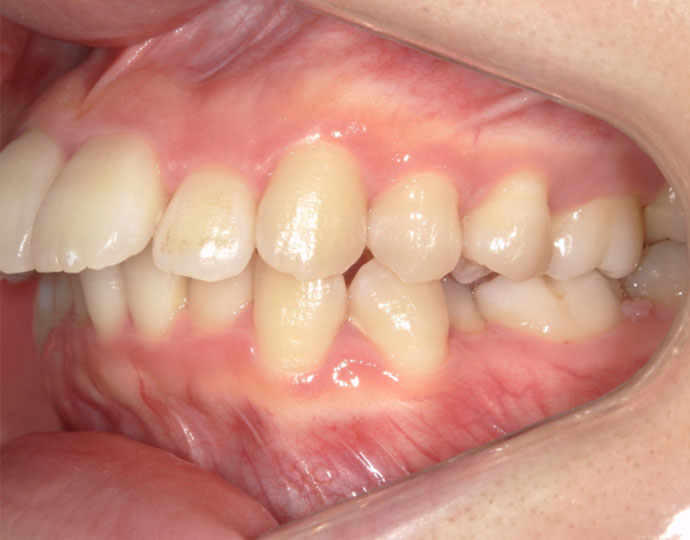

ワイヤー治療 叢生+上顎前突不正咬合 治療例

治療前

治療後

| 患者様 | 女性 19歳 |

| 主訴 | 歯並びと口元を綺麗にしたい。 |

| 診断 | 叢生歯列を伴う上顎前突不正咬合 |

| 治療方針 | 上顎左右第一小臼歯、下顎左右第二小臼歯の抜歯 |

| 治療に使用した装置 | セルフライゲーションブラケット インプラントアンカースクリュー×2 |

| 治療期間 | 2年6カ月 |

| 治療回数 | 24回 |

| 治療費(自費診療) | 880,000円(税込み) |